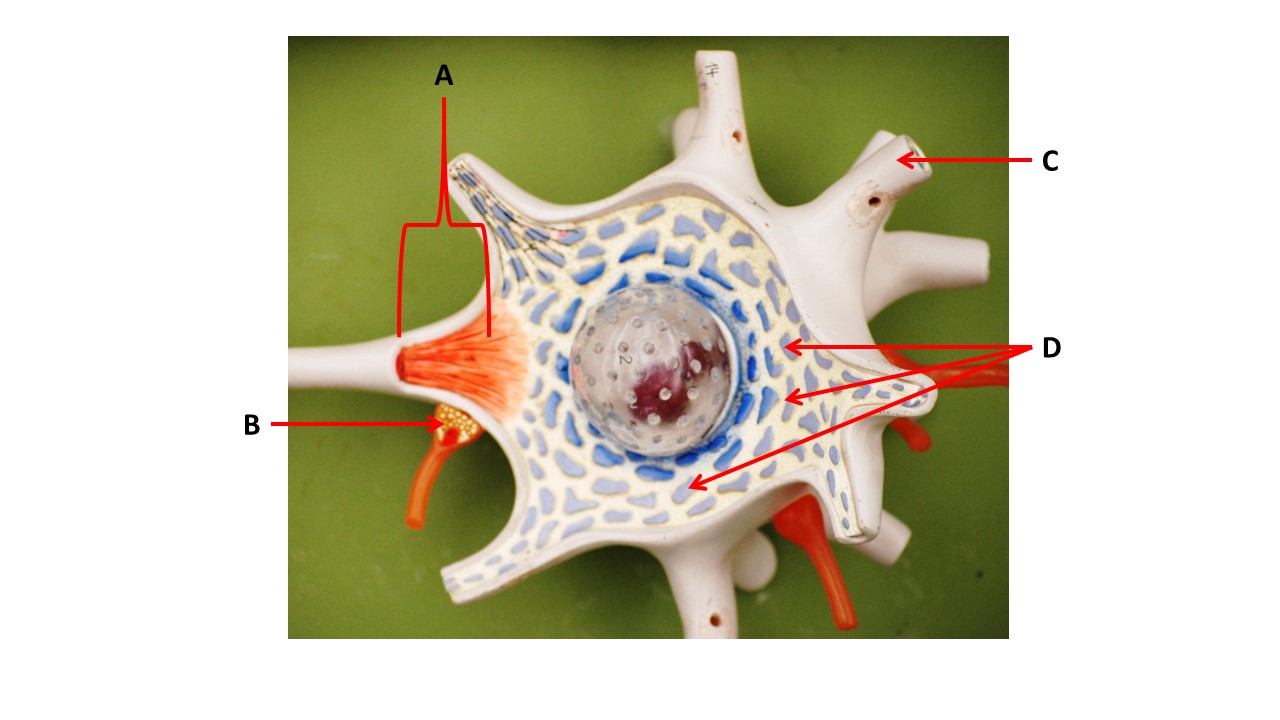

Name the region within bracket D.

medulla

Name the region of tissue surrounding the tip of arrow E.

lateral horn

Name the region of tissue surrounding the tip of arrow B.

dorsal horn

Name the structure at the tip of arrow K.

ventral root

Name the region of tissue surrounding the tip of arrow J.

ventral column

Name the region of tissue surrounding the tip of arrow E.

lateral horn

Name the region of tissue surrounding the tip of arrow N.

dorsal column

Name the deep groove at the tip of arrow G.

anterior median fissure

Which structure(s ) would be found in the area at the tip of arrow D.

cell bodies of interneurons

Name the region of tissue surrounding the tip of arrow E.

ventral horn

Name the region within bracket G.

gray commisure